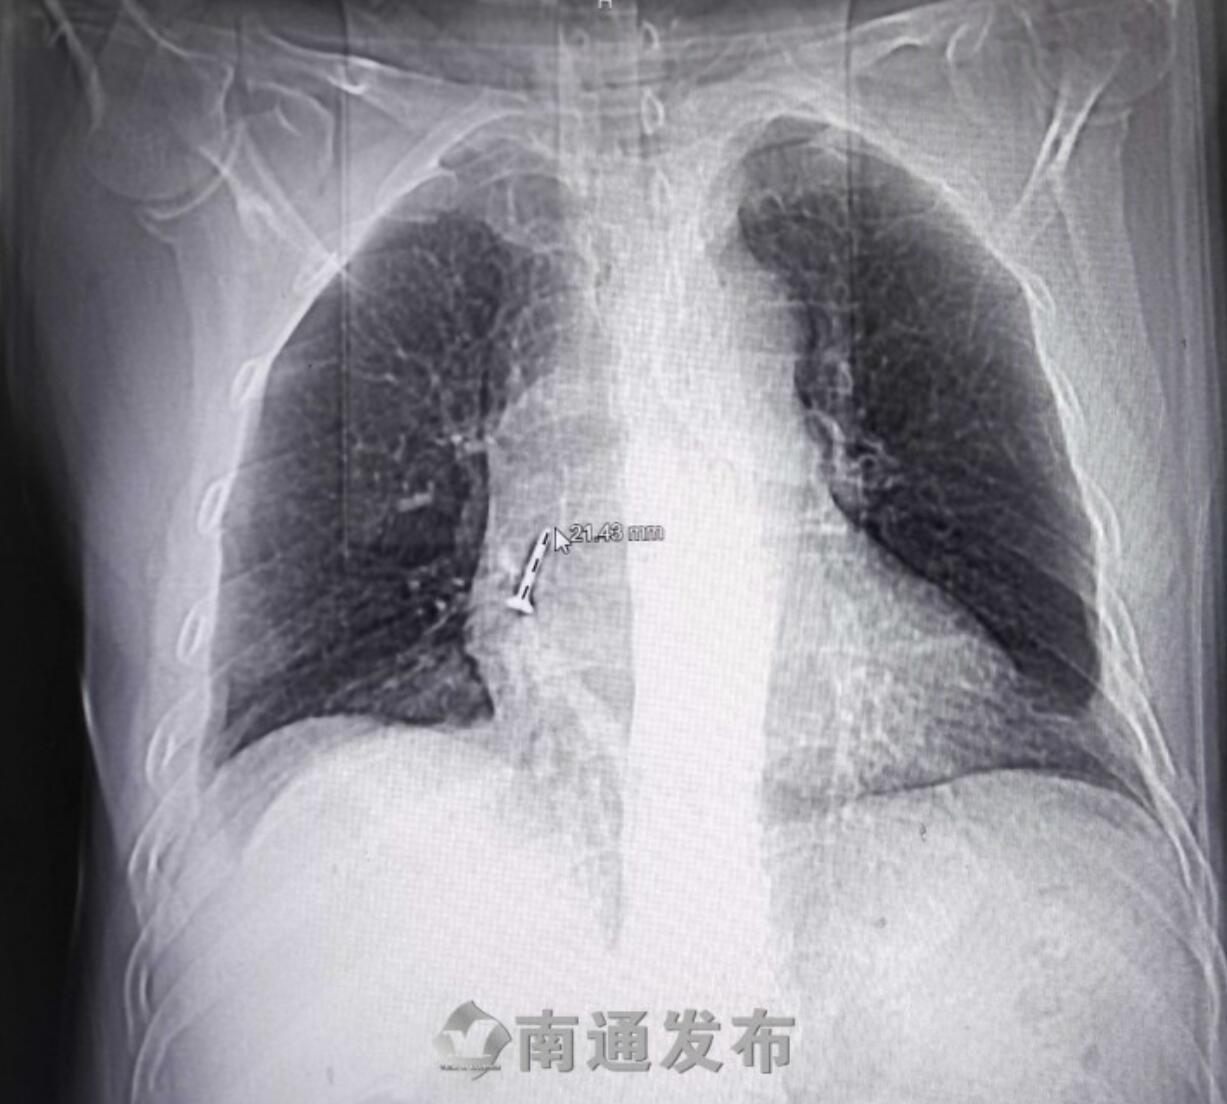

22日,吴大伯在儿子的陪同下来到南通市第六人民医院呼吸与危重症中心就诊。“从他带来的影像片上看有一个亮点,一看就是一颗螺丝钉,追问病史,原来这个患者是一个木工,但他自己也想不起来这颗螺丝钉是什么时候、怎么掉进去的,回忆可能是在抬头安装吊顶的时候,嘴巴刚好微微张开,螺丝钉不经意间落入气管。”南通六院呼吸与危重症中心专科副主任史广林告诉记者,因为螺丝钉的头子很尖锐,有可能损伤血管,所以为了明确螺丝钉在气管内的情况,又安排患者做了增强CT,评估病情。发现万幸的是,螺丝钉没有损伤到血管,相对安全,于是决定在局部浸润麻醉下经支气管镜为患者取出异物。

“入镜顺利,镜下可见一黑色异物堵塞在右肺下叶基底开口处,因为反复嵌顿,造成气道阻塞,出现了炎症感染,气道里有很多黄色黏痰。在钳取过程中,反复调整钳取角度,顺利取出约2.5厘米长的螺丝钉,顺便把痰液进行了清洗。”史广林主任介绍,整个过程十分顺利,术后,患者的剧烈咳嗽症状基本没有了,呼吸又重新顺畅了起来。但因为时间比较长,导致肺部炎症,还需要经过一段时间的消炎治疗。